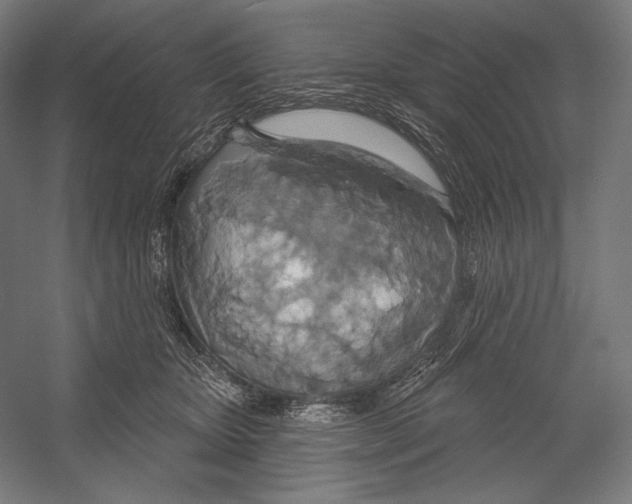

Image 420471

Precipitate

Organization

HWI